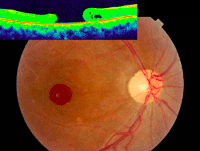

Agujero macular asociado a uveítis

Entre las posibles alteraciones maculares de origen inflamatorio, Nussenblatt

17 describe el agujero macular como una complicación rara de las uveítis, siendo más frecuente el agujero macular idiopático o senil, postoperatorio o secundario a tracción vítreo-macular o membrana epiretiniana, pero infrecuente en la inflamación de segmento posterior.

En la literatura hay reportados 55 casos de agujero macular asociado a uveítis (

Tabla 3), 35 de ellos con agujeros maculares asociados a enfermedad de Behçet (

Figura 16 y

Figura 17).

Figura 16. Paciente con uveítis posterior asociada a enfermedad de Behçet que tras un brote inflamatorio desarrolla un agujero macular completo con fluido submacular, que se resuelve tras cirugía de vitrectomía, consiguiendo un cierre completo.

Figura 17. Agujero macular de espesor completo y gran diámetro secundario a enfermedad de Behçet.

La patogénesis de los agujeros maculares asociados a inflamación es desconocida. Se cree que la inflamación intraocular induce cambios como la licuefacción del vítreo y contribuye al desprendimiento del vítreo posterior, lo cual produciría la primera constricción. El desarrollo de membrana epiretiniana sería la causa de la tracción tangencial. Finalmente, los focos de coriorretinitis y la presencia de edema macular provocan fragilidad en el tejido retiniano, facilitando la rotura de la retina y la formación de agujeros maculares. Tratando el proceso inflamatorio y limpiando el vítreo del infiltrado inflamatorio podrían aliviarse esas tracciones e incluso favorecer el cierre espontáneo de algunos agujeros maculares, como está descrito en la literatura

18. Otros casos requerirán cirugía de vitrectomía

19.